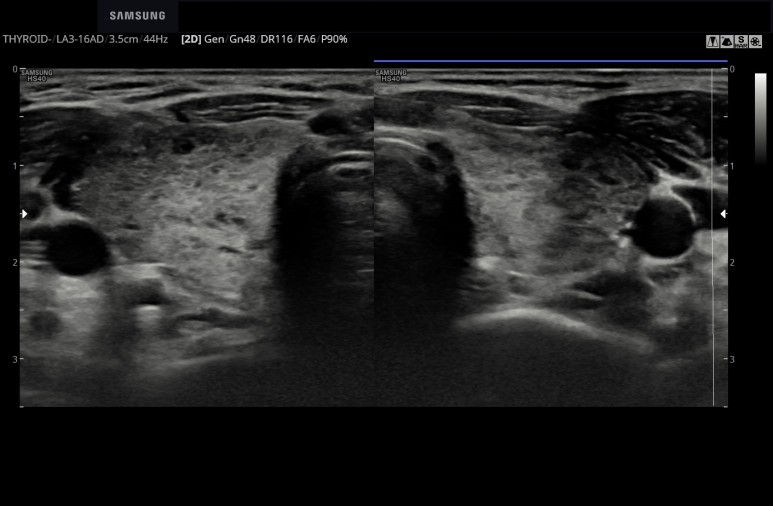

20대 후반 여자 "목이 부은 느낌이 있다. 오른쪽이 비대칭적인거 같다." 시진상 전반적인 비대가 의심 초음파 시행 전반적인 비대, 양측에 볼록한 갑상선을 확인 실질은 전반적으로 거친 양상 전후 직경이 커졌다. 혈관상은 증가한것 같으나.....